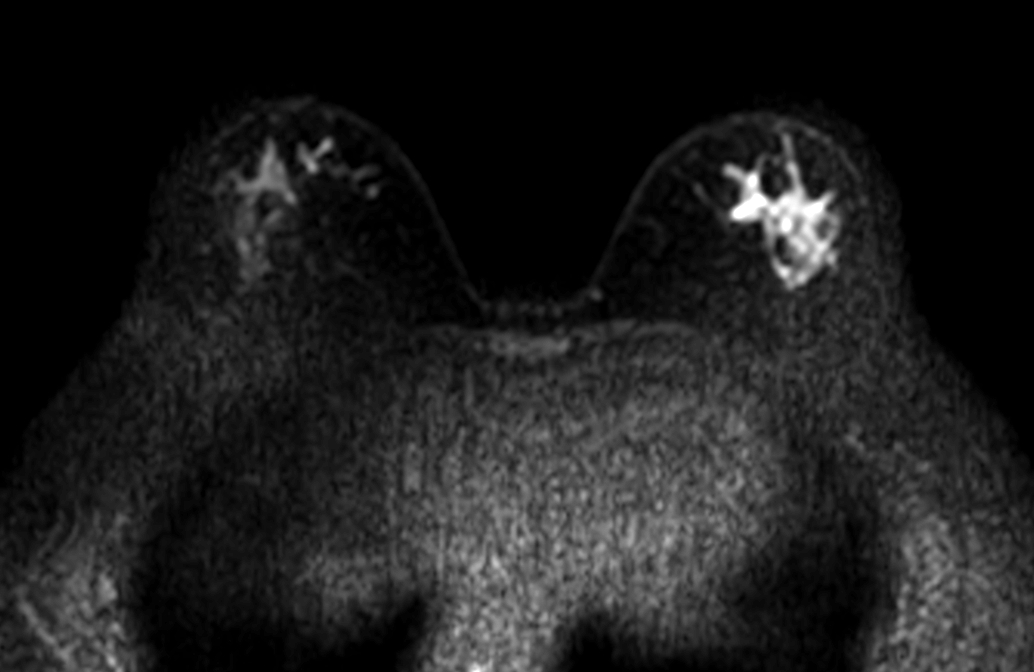

Axial DWI (b100)